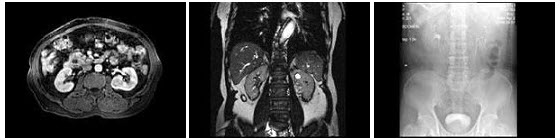

63、多项选择题

男,67岁,无痛性血尿1月,IVP和MRI检查如图示,下列说法正确的是()

A.IVP示左侧中组肾盏未见显影

B.左肾中部内侧可见类圆形不均匀信号肿块突向外

C.左肾上极可见一T2WI为高信号圆形病灶,边界清楚

D.左肾中部病灶考虑为小肾癌

E.左肾上极病灶考虑为肾囊肿